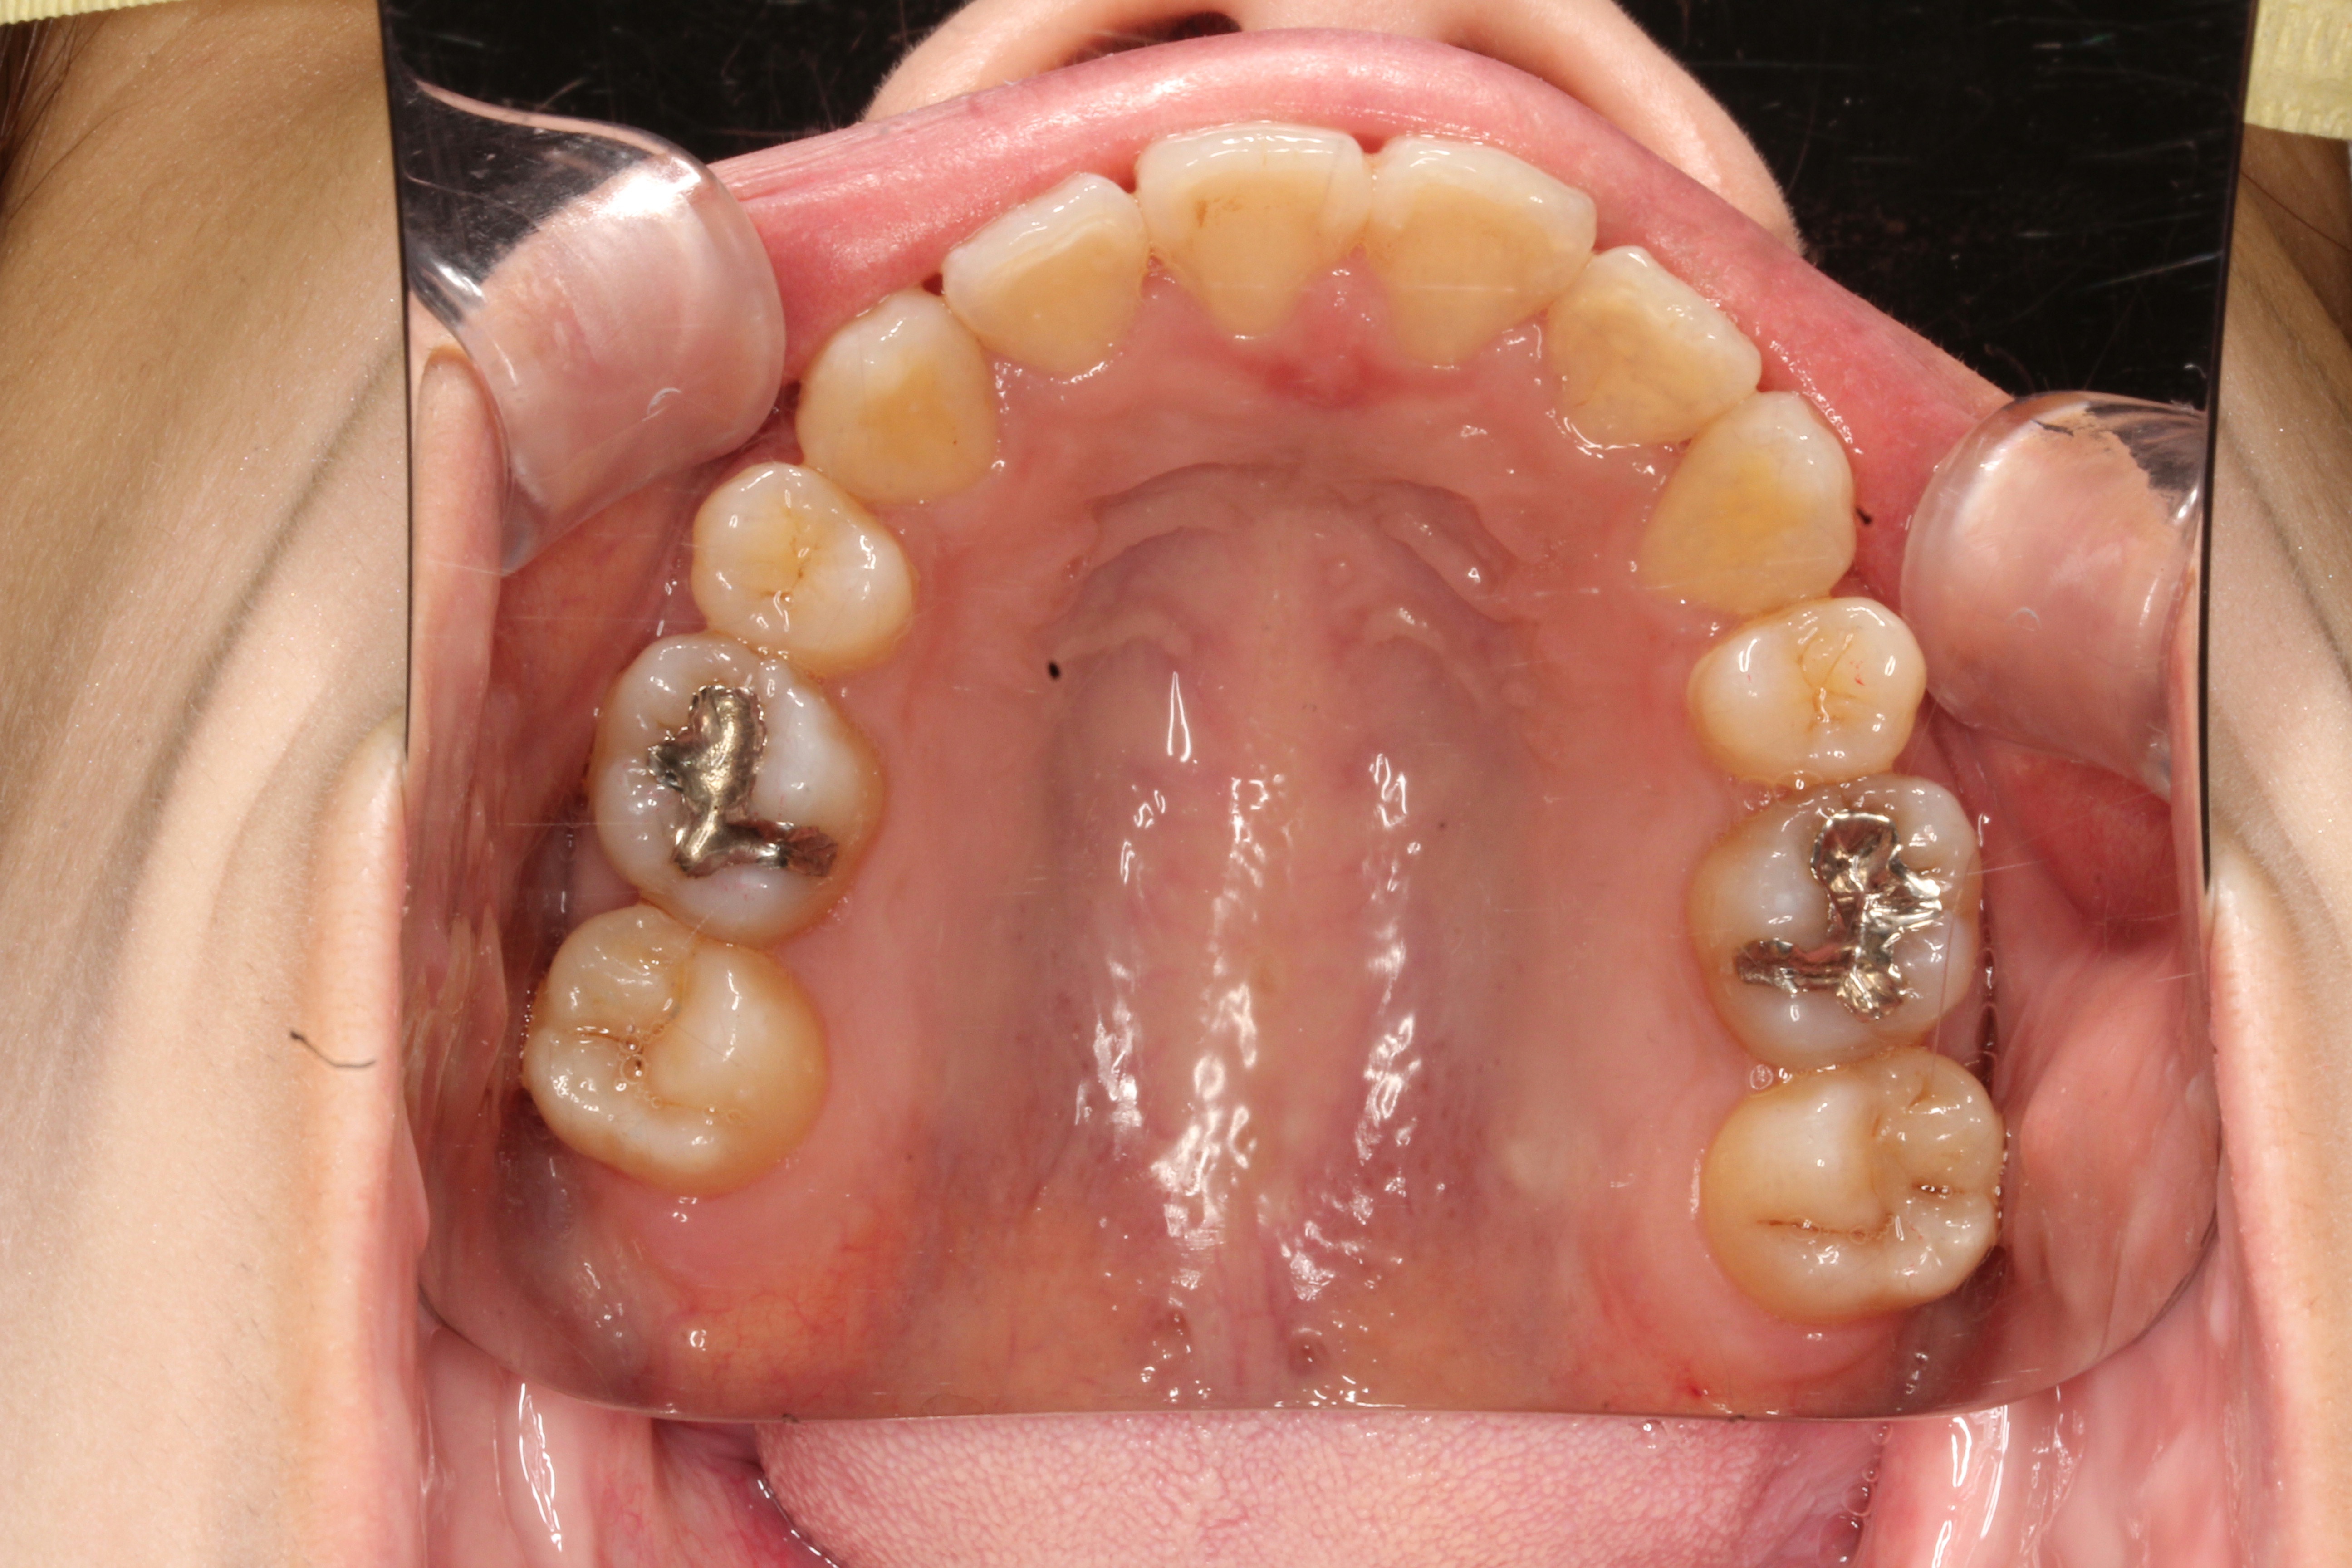

軽度の出っ歯を治したい

年齢層 20代

性別 女性

主訴 【主訴】出っ歯を治したい 【診断・症状】上下凸凹、出っ歯(上顎前突)

治療費用 検査・診断:38,500-/裏側矯正治療:1,397,000-(※全て税込)

治療期間 約2年半(33回)

抜歯 有(上4,4)

矯正の装置 裏側矯正(舌側矯正)

副作用、リスク 歯肉退縮,歯根吸収,疼痛,咬合の違和感,装置の違和感,虫歯,歯肉炎

case13_軽度の出っ歯_before

Before

case13_軽度の出っ歯_after

After